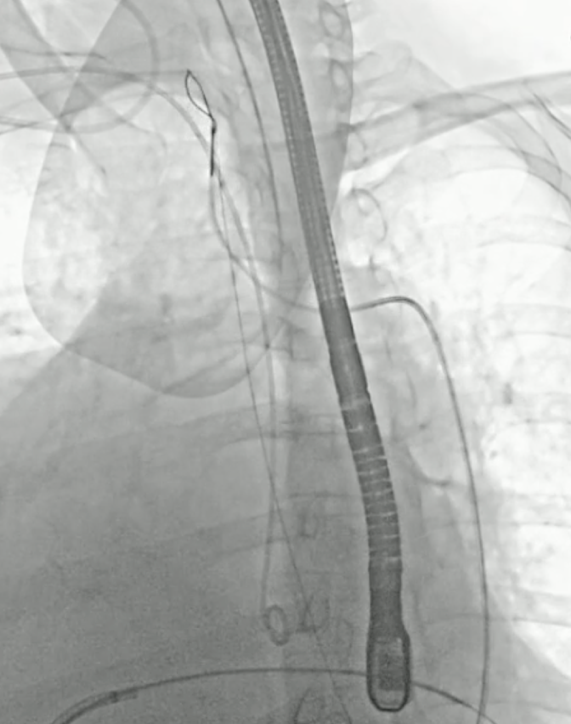

小球囊预扩张

20mm球囊预扩张

双平面造影确认植入位置

释放完成

球囊后扩后,超声确认植入位置合适,形态满意,造影未见反流